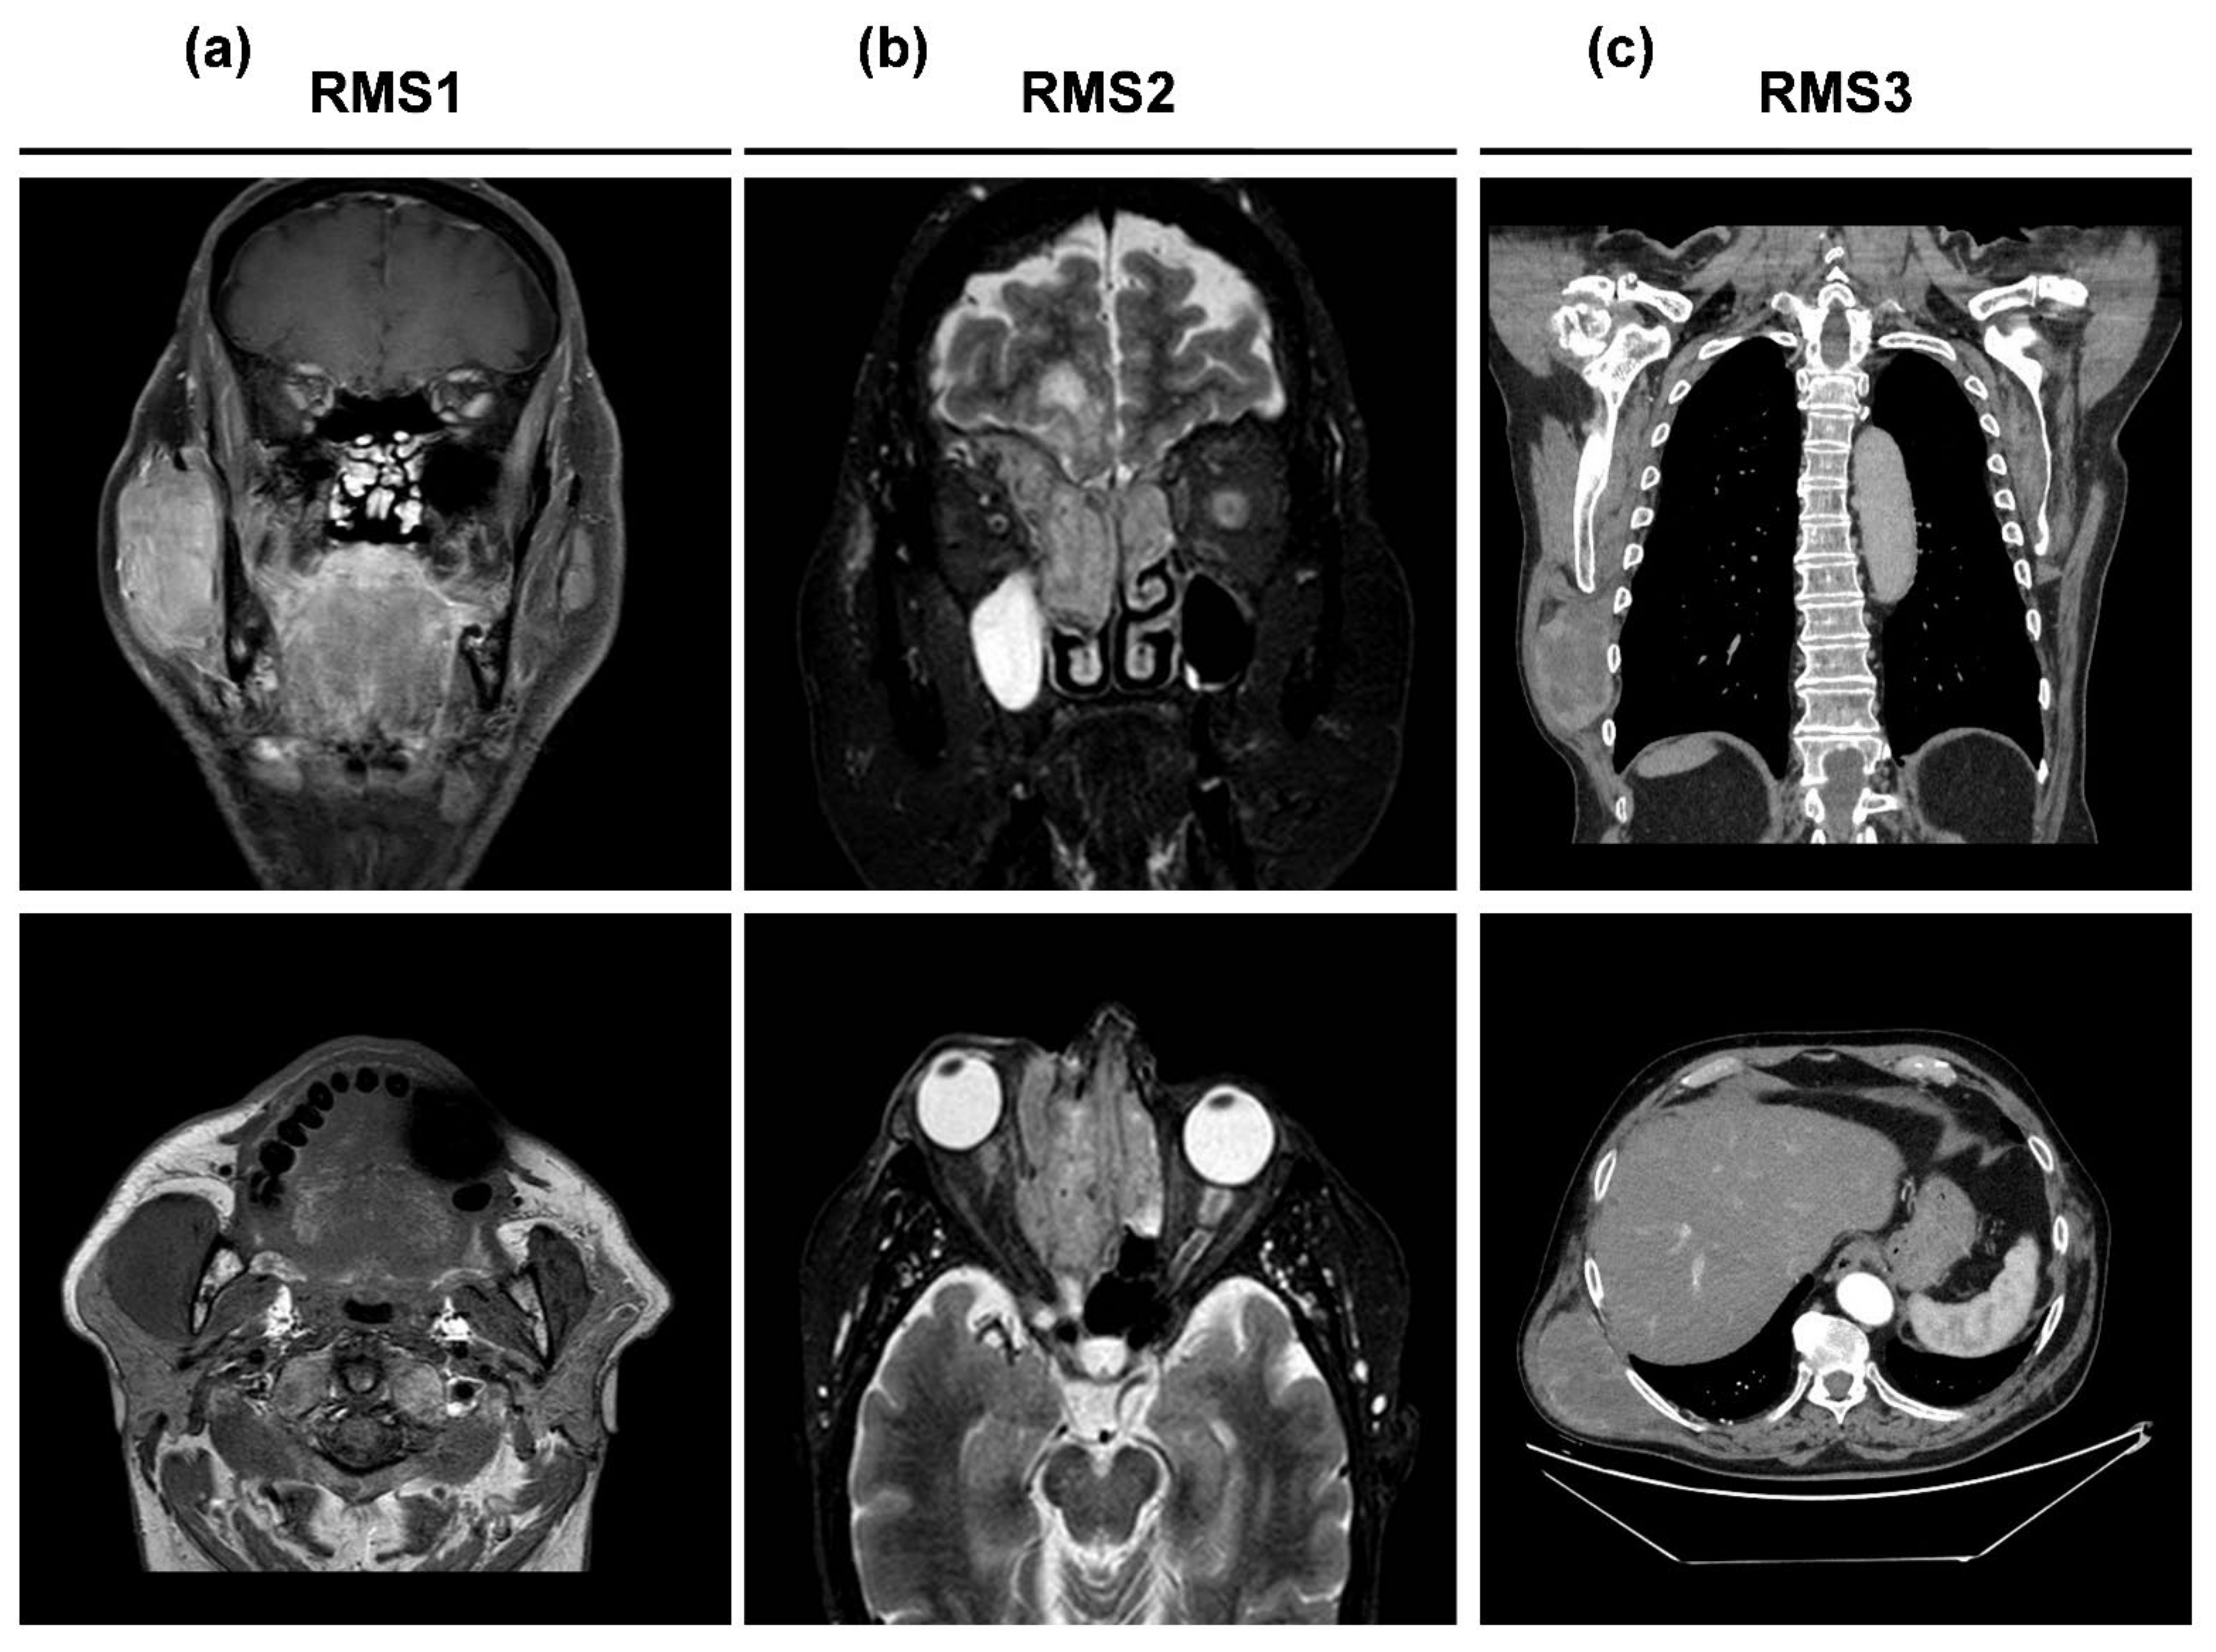

| Patient | Gender | Age at Surgery | Site | Size (cm) | Histological Subtype | IHC Analysis | Surgical Margins | Radiotherapy Post-Surgery | Chemotherapy Post-Surgery | Follow-up Months |

|---|---|---|---|---|---|---|---|---|---|---|

| RMS1 | male | 74 | masseterine parotid region | 10 × 9 × 3 | Spindle cell/sclerosing RMS | VIM+ MyoD1+ CD56+ Desmin+ Myoglobin+ Myogenin+ SMA+ CD34+ AE1-AE3 cytokeratin+ MDM2+ S100– STAT6– P63– | R1 | adjuvant IMRT radiotherapy treatment 60 Gy | Doxorubicin4 cycles Gemcitabine 3 cycles | 11 |

| RMS2 | female | 72 | ethmoid-orbital region | 1.2 × 0.8 | Alveolar RMS | MyoD1+ Desmin+ Myogenin+ AE1-AE3 cytokeratin– MDM2– S100– Synaptophysin– CD99– CD 45– GFAP– | na | na | na | 7 |

| RMS3 | male | 77 | latissimus dorsi | 15 × 11.5 × 7.5 | Pleomorphic RMS | MyoD1+ Desmin+ Myogenin+ SMA+ CD34– AE1-AE3 cytokeratin– S100– | R0 | na | na | 1 |